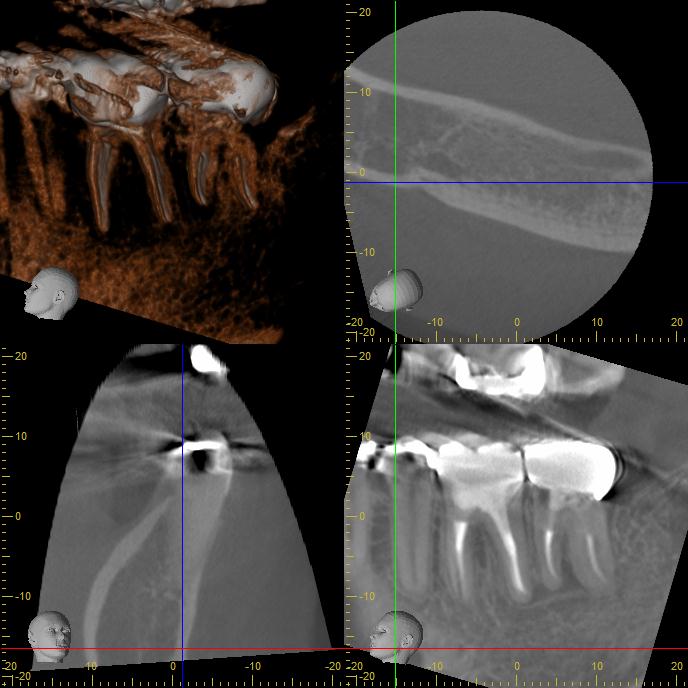

補綴後の写真です。被せ物が歯にピッタリと適合していることが確認できます。

術後のCT画像です。根尖部に認めた透過像が消失しているのが分かります。